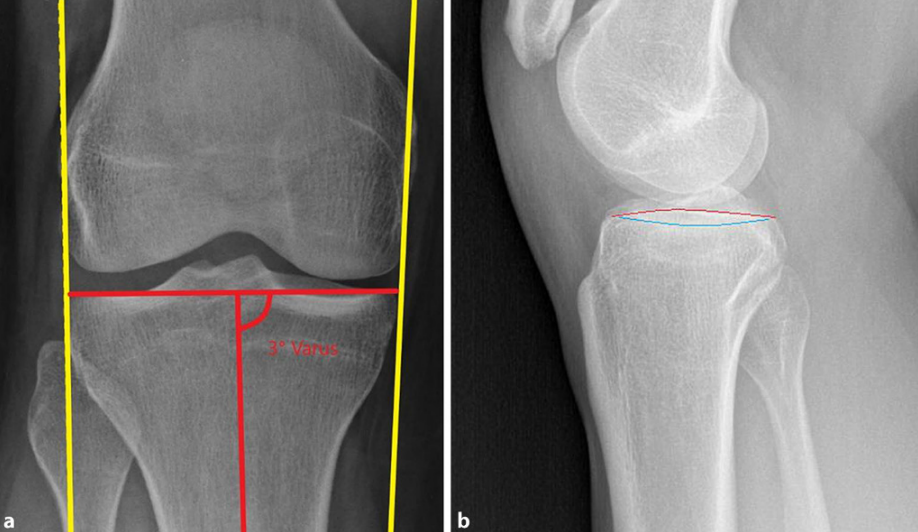

胫骨平台宽度是膝关节正位片上胫骨近端关节面内缘至其外缘的距离。伴 有外侧平台关节面塌陷的胫骨平台骨折常伴有平台增宽,随着关节面复位,平台宽度大多恢复正常。 因此,平台宽度也成为评估关节面复位质量的间接指标,并与患者长期预后相关。

如果关节面复位良好,单纯胫骨平台增宽5~10mm对膝关节功能的影响并不明显因素 ,也不是未来膝关节置换的独立危险因素。

胫骨平台后倾角是矢状面上胫骨平台关节面与胫骨干垂线的夹角。根据胫骨平台骨折三维损伤机制分型,屈曲型损伤的胫骨平台后倾角增加,而过伸型损伤的胫骨平台后倾角减小或消失,甚至为负值。后倾角的变化既可能仅局限于内侧或外侧平台,也可能同时累及双侧平台,在骨折复位时要针对性恢复对应平台的后倾角。

一般来说外侧平台后倾角(平均7.5°)稍大于内侧平台后倾角(平均5.2°),而且两膝的内外侧平台后倾角基本对称,因此在术前计划和术中 复位时可以参考健侧膝关节的平台后倾角。